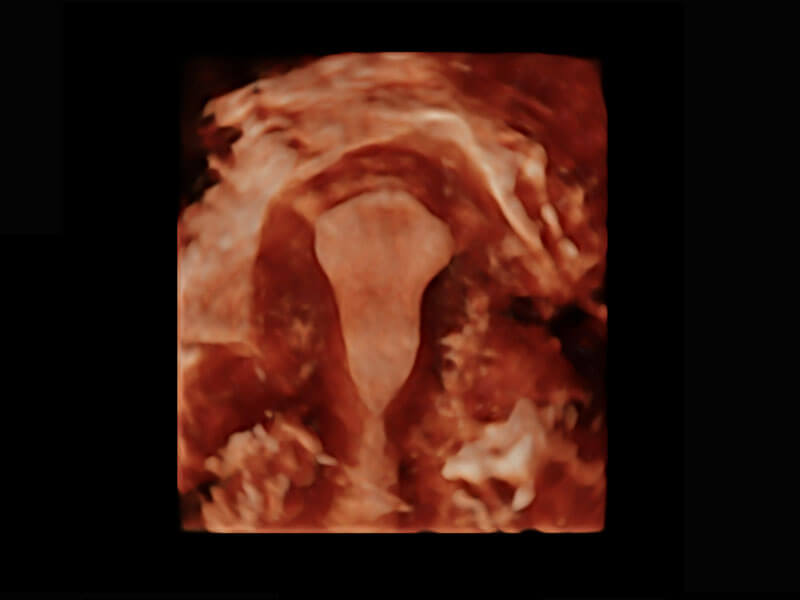

P60搭载一系列胎儿心脏成像技术,实现精细的胎儿心脏评估。

四腔切面

右室双出口

胎心容积成像